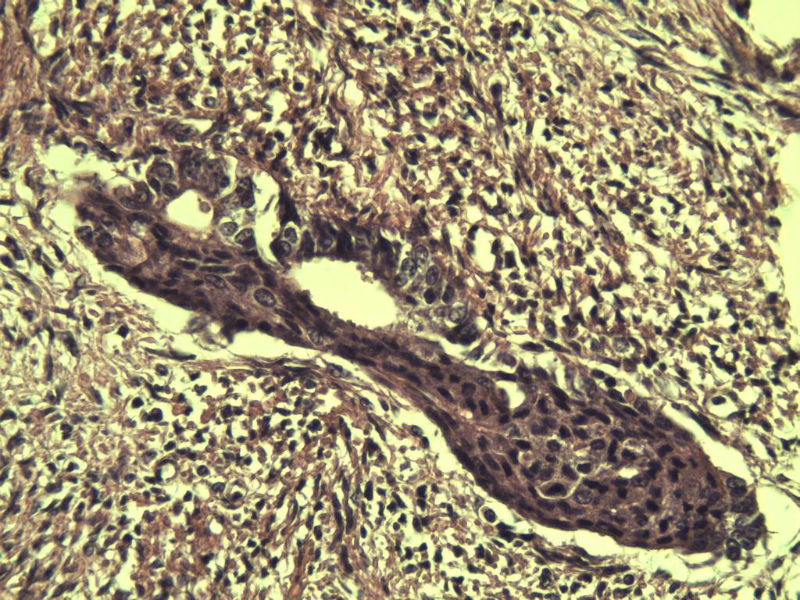

42岁 月经不规则一年 b超发现子宫肌瘤 行全子宫切除术  我取材时发现子宫颈管上段有一质地较硬区 2*1cm  请各位老师看看 是子宫内膜癌不? 谢谢了!

这是子宫颈管上段

肌层内腺体的特点:1、无内膜间质。

2、有鳞化。

3、无异型。所以应该还是个良性病变

非典型性息肉样腺肌瘤。

3.镜下特征:上皮成分由杂乱无章排列的不规则的子宫内膜型腺体构成,可以是立方形到矮柱状或假复层。显示有广泛的鳞化区域(本例图11-17均显示鳞化),表现为圆形的“桑葚”(图16-17);间质主要由平滑肌构成,且混有纤维组织。